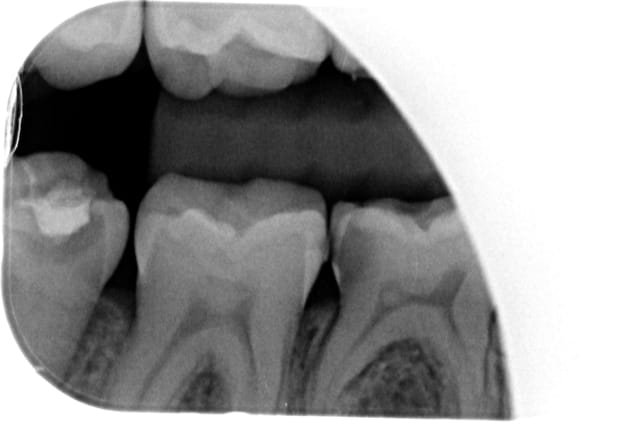

je reçois ce jour cette nouvelle patiente trisomique qui présente des agénésies multiples.

le traitement odf est phase de contention

55,65,75 et 85 ont été conservées

mais pour 65 75 et 85 c'est endo je pense

D'après la radio, tu vas te retrouver avec des cavités occluso proximales. Pour moi c'est compo direct ou indirect.

Le délabrement sur 65 et encore plus sur 75 seront plus qu'occluso-proximaux

La restauration directe ou indirecte ne concernera que 85 dans le meilleur des cas.